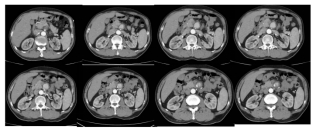

老徐,58岁,常年务农,有慢性胃炎史。两个月前,他突然开始肚子疼,还伴有黑便。“以为是胃病又犯了,忍忍就过去了。”老徐说。就这样疼了十天,忍了十天,居然自己好了。可过了一个多月,腹痛突然卷土重来,比以往任何时候都剧烈!疼得他直不起腰,连背都跟着疼,吃不下饭,睡不着觉。老徐害怕了,辗转多家医院,CT、胃镜、抽血化验都做了,可就是查不出原因。直到他来到中日医院,通过增强CT及血管外科医生的确诊,终于揭开了真相——肠系膜上动脉夹层,一个直径2.8厘米的夹层动脉瘤已经形成!

腹部ct